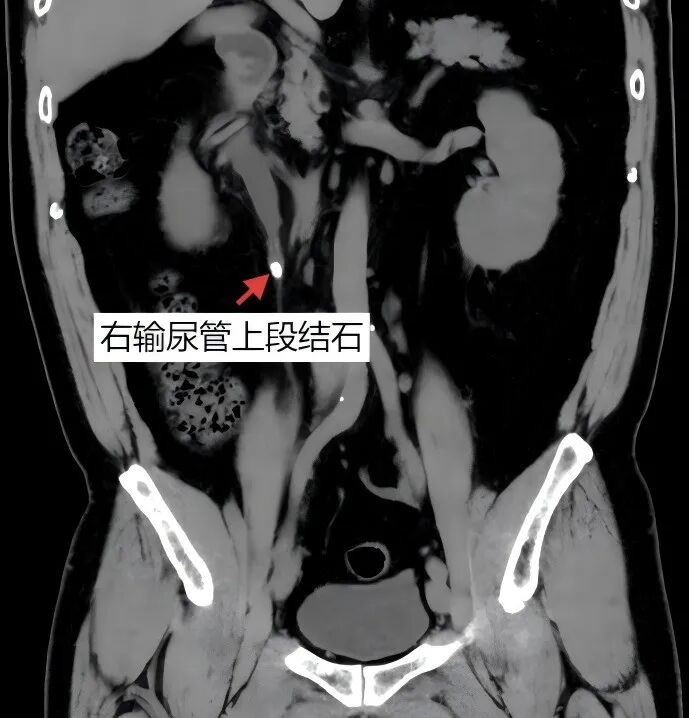

某天上午,42岁的张先生(化名)正悠闲地喝着咖啡,突然右侧腰腹一阵剧痛袭来,疼痛难忍!呕吐、尿频、血尿……这些症状让他瞬间明白了什么叫“痛到怀疑人生”。于是,他火速赶往香港大学深圳医院泌尿外科,找到了碎石团队。经过检查,团队发现张先生的右输尿管上段藏着一颗约10mm的结石,还引发了轻度肾积水。

02.高科技“精准”碎石,让结石无处遁形

说到体外冲击波碎石术,那可是结石界的“降维打击”!原理很简单:用高能冲击波从体外精准“轰炸”结石,让它粉身碎骨,最后随尿液排出体外。

术前,团队为张先生做了全面检查,确保万无一失。术中,碎石机“锁定目标”,将结石“震碎”。全程无切口,张先生还和医生聊了会天!术后,张先生的疼痛迅速缓解。更让他惊喜的是,第3次排尿时居然看到了黄色细砂——这是“震碎”的结石,也是治疗成功的铁证!一周后复查,结石彻底消失,肾积水也无影无踪。